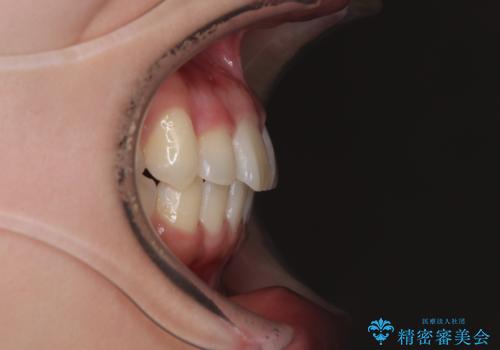

- 上下前歯のデコボコを気にして来院された患者様です。

僅か8ヶ月という短期間で、綺麗な歯列に仕上がりました。